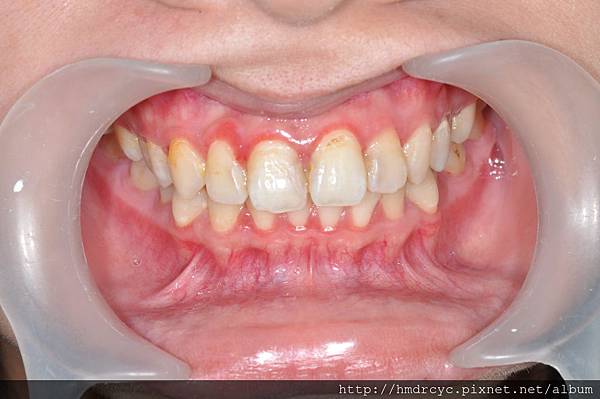

高雄的T先生有相同問題

單純牙肉發炎沒有骨頭吸收

洗牙治療兩天後 牙肉消腫回到原本位置